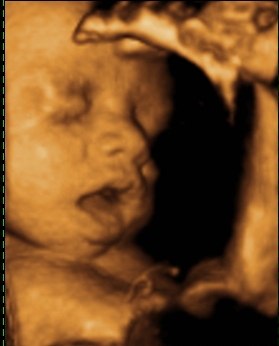

så var vi til 3D scanning i fredags. Så vild en oplevelse.. Hun er bare helt perfekt.

hun vejede 1423g, og så var hun en uge foran så det var da super dejligt at vide at lille pigen har det super og lever luxus derinde i maven

vi var heldige med at hun var rigtig aktiv plus vi også så hende med åbne øjne